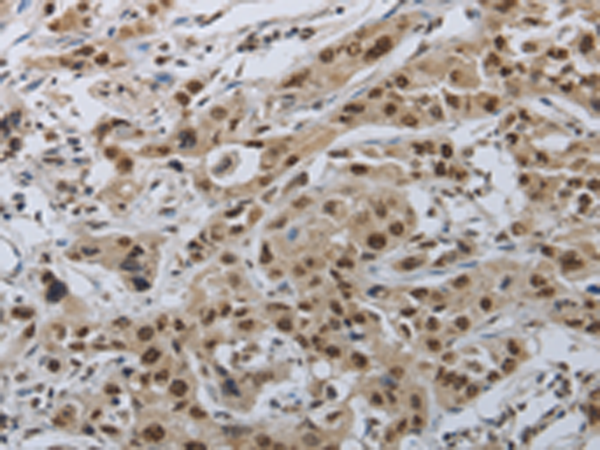

分类: 科研抗体货号: P04417别名: PD1, PD-1, CD279, SLEB2, hPD-1, hPD-l应用: IHC反应种属: Human